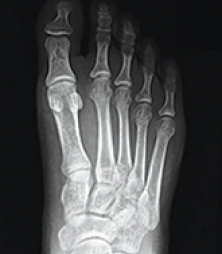

What Does A Correction Look Like On X-Ray?

xray Normal Foot

xray Traditional 2D Surgery

"Cut & Shift" approach leaves an unstable joint

xray Lapiplasty® 3D Bunion Correction™

Alignment is restored & unstable joint is permanently secured